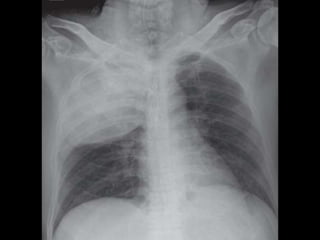

Bulging Fissure Sign